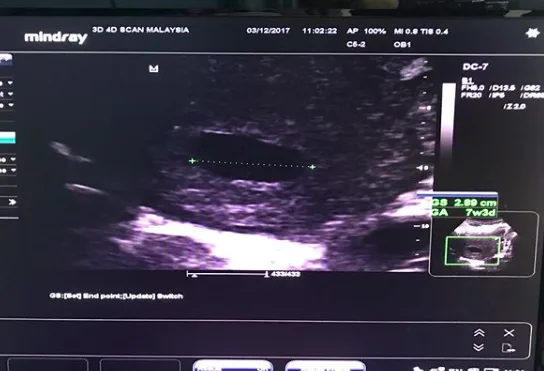

Tahniah team murai.my ucapkan kepada pasangan romantis Norman Hakim dan Memey Suhaiza apabila dikhabarkan bakal menimang cahaya mata ketiga tidak lama lagi.

Pengumuman khabar gembira secara rasminya telah dikongsi Norman di Instagram miliknya sebentar tadi dan begitu teruja menerima perkhabaran tersebut. Tambah Norman, ini merupakan satu kejutan untuknya dan dia merupakan individu terakhir mengetahui mengenai kehamilan isterinya.